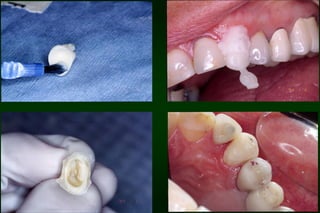

After 1 week

After 2 months